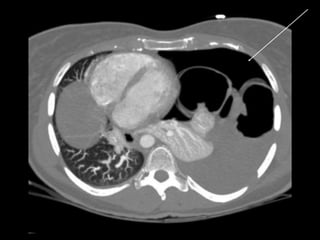

Chest CT scan :-

• Intrapleural gas along with loculated pneumothoraces.

• Pleural effusion, pneumothorax.

RADIOLOGICAL FINDINGS Chest X-ray:- • Hyper translucency between the lung & thoracic cage. • Razor sharp border of the collapsed lung. • Shifting of mediastinum on the opposite side of injury. Chest CT scan :- • Intrapleural gas along with loculated pneumothoraces. • Pleural effusion, pneumothorax. Chest Ultrasound :- • Smooth horizontal echogenic lines are seen above and below the pleural lines. • Absence of lung sliding and B - lines.